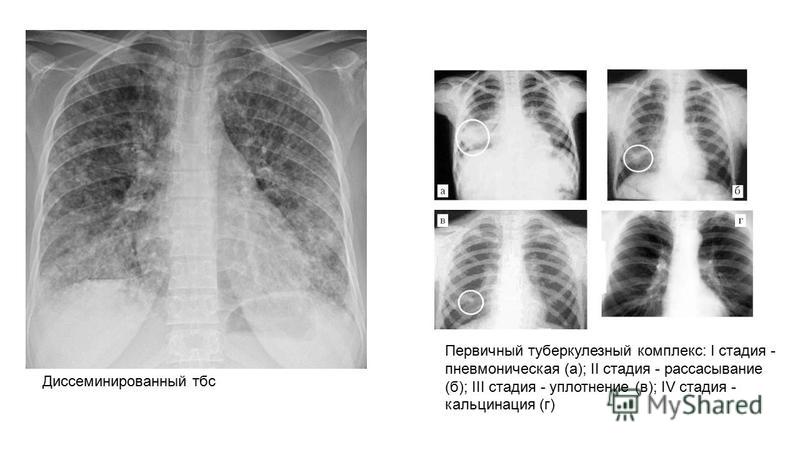

Симптомы и лечение инфильтративного туберкулеза легких

Раздел: Снимки-откровения